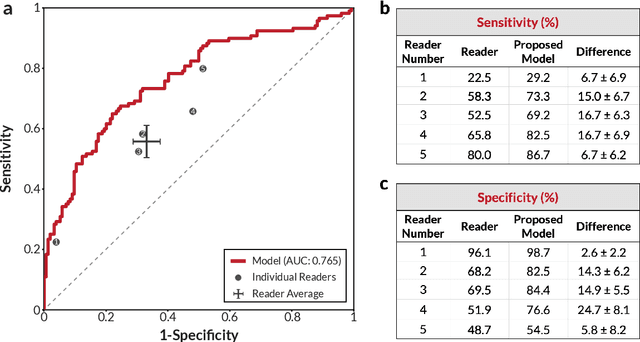

Robust breast cancer detection in mammography and digital breast tomosynthesis using annotation-efficient deep learning approach

Breast cancer remains a global challenge, causing over 1 million deaths globally in 2018. To achieve earlier breast cancer detection, screening x-ray mammography is recommended by health organizations worldwide and has been estimated to decrease breast cancer mortality by 20-40%. Nevertheless, significant false positive and false negative rates, as well as high interpretation costs, leave opportunities for improving quality and access. To address these limitations, there has been much recent interest in applying deep learning to mammography; however, obtaining large amounts of annotated data poses a challenge for training deep learning models for this purpose, as does ensuring generalization beyond the populations represented in the training dataset. Here, we present an annotation-efficient deep learning approach that 1) achieves state-of-the-art performance in mammogram classification, 2) successfully extends to digital breast tomosynthesis (DBT; "3D mammography"), 3) detects cancers in clinically-negative prior mammograms of cancer patients, 4) generalizes well to a population with low screening rates, and 5) outperforms five-out-of-five full-time breast imaging specialists by improving absolute sensitivity by an average of 14%. Our results demonstrate promise towards software that can improve the accuracy of and access to screening mammography worldwide.